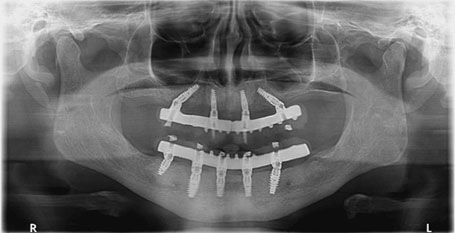

Full mouth implants placement

Firstly, the doctor will check for the 3-dimensional x-rays of the upper and lower jaw. Generally, we place implants on the same day of the removal of the teeth. However, if bone condition is compromised then we might have to do sinus lifting or bone grafting procedure and we need to wait for implant surgery so that bone can get matured. It is not required in every case, mostly, we place 4 or 6 implants on the same day. We can give temporary prosthesis within a week in such cases if implant stability is satisfactory. After 3 to 4 months, you will get permanent teeth and that will give you natural looks and feeling.

Full mouth implant placement with fixed teeth (4 implants in upper jaw whereas 5 implants in lower jaw)